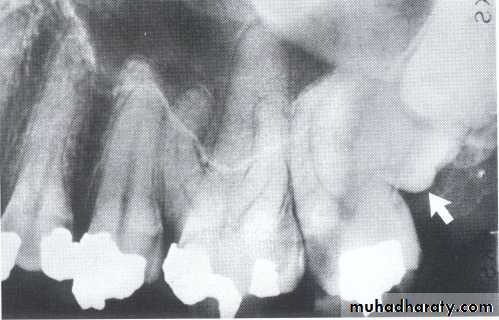

Dilaceration of the crown

specimenX-Ray

Dilacerated root. The apical portion of the root is bent buccally or lingually into the plane of the central ray. Note the halo in the apical region, produced by the PDL

space (arrow).